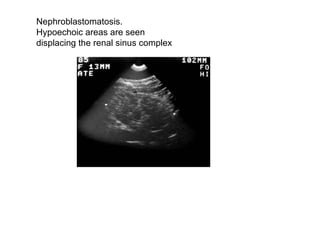

Nephroblastomatosis.  Hypoechoic areas are seen  displacing the renal sinus complex